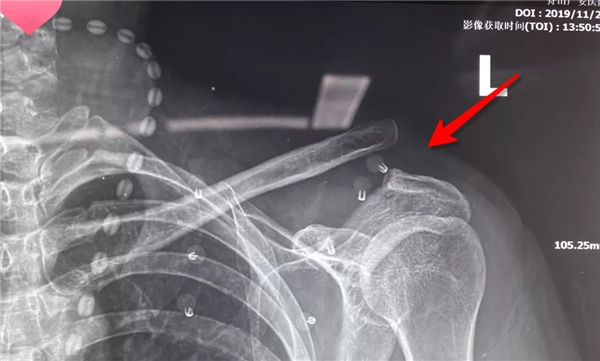

據(jù)羅軍主任介紹,肩鎖關(guān)節(jié)脫位是一種較為常見的外傷性脫位,對(duì)于完全移位的Rockwood 4-6型脫位,以往的手術(shù)治療大多使用鎖骨鉤鋼板復(fù)位固定,包括鉤鋼板內(nèi)固定,喙鎖間螺釘固定術(shù),鎖骨外側(cè)端切除,肩鎖韌帶重建等術(shù)式,但是這些技術(shù)都存在著一定程度的缺陷,一是創(chuàng)傷較大,術(shù)后經(jīng)常出現(xiàn)肩部疼痛、活動(dòng)受限、肩峰骨質(zhì)溶解、肩峰下撞擊、應(yīng)力性骨折、脫鉤失效等并發(fā)癥,二是后期還需要二次手術(shù)取出鋼板。

傳統(tǒng)手術(shù)方式——大切口上鋼板